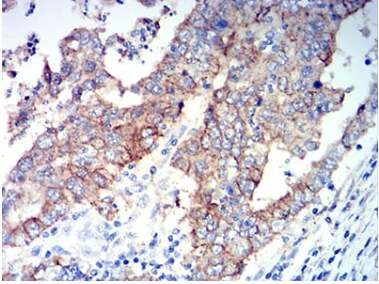

ALDH1A1 Mouse Monoclonal antibody[2G1G4]

IHC    1/200 - 1/1000